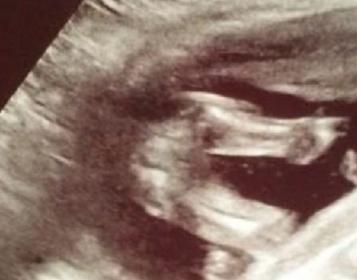

17+5 Potty Shot, Girl or Boy???

This ultrasound was only 1 minute long (seriously!). My phone had died, too. ANYWAYS, this is the only picture I got. Babe had legs closer together in the first 30 secs and while she was measuring, which I told her no I want to know gender. Which she didnt even say, just printed this picture...So frustrating. I was also telling her if its a girl I want you to point out the labia. lol

My anatomy scan is May 13th at the American hospital in Seoul. I am going to try to wait... Until then, could anyone tell boy or girl?

These are the same picutres just different lighting.